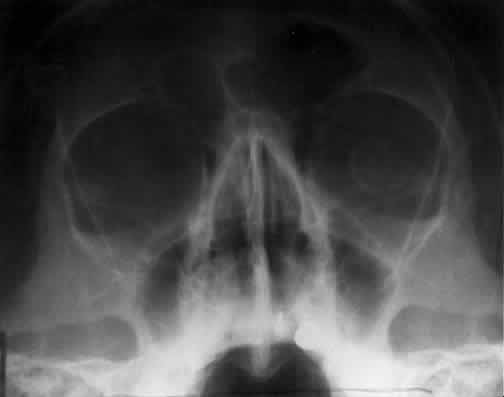

The posterior segment of the lateral wall courses posterior medially and can be seen in anterior projections such as the Caldwell view. This view allows direct visualization of the greater sphenoid wing contribution to the lateral wall. Bone density changes in the greater wing of the sphenoid, such as from a meningioma, can be detected. Fractures of the lateral orbital wall can occur from blunt trauma to the malar prominence. The zygomatic complex fracture (tripod) results from separation of the zygomatic-frontal, zygomatic-temporal, and the zygomatic-maxillary sutures. These fractures are associated with an inferior displacement of the malar prominence and a rounded lateral canthus (Figs. 8 and 9).

Fig. 8. A zygomatic complex fracture (tripod) after blunt trauma to the right cheek. Note the right zygoma is inferiorly displaced. (a, zygomatic-frontal suture separation; b, orbital rim disruption; c, opacification of maxillary sinus)

Fig. 9. Bilateral zygomatic complex and LeFort II fracture after reduction using fixation plates. Caldwell projection shows good alignment of orbital margin and zygomatic bones.